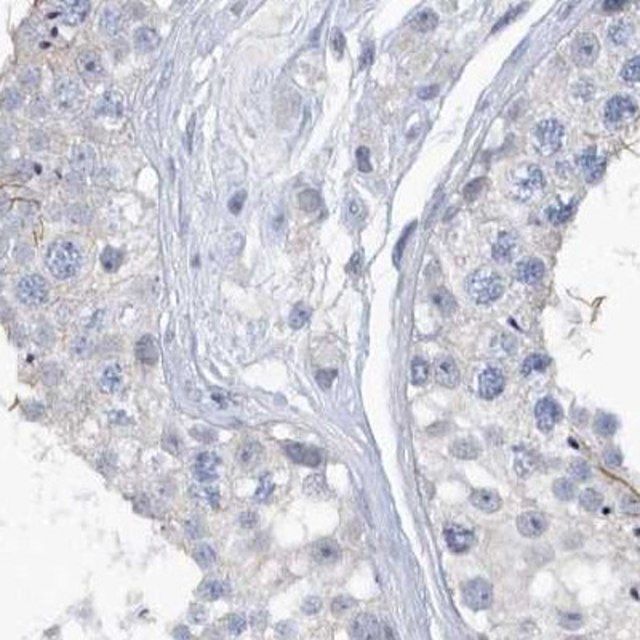

The Human Protein Atlas project can be subdivided into three efforts: Human Tissue Atlas, Cancer Atlas, and Human Cell Atlas. The antibodies that have been generated in support of the Tissue and Cancer Atlas projects have been tested by immunohistochemistry against hundreds of normal and disease tissues and through the recent efforts of the Human Cell Atlas project, many have been characterized by immunofluorescence to map the human proteome not only at the tissue level but now at the subcellular level. These images and the collection of this vast data set can be viewed on the Human Protein Atlas (HPA) site by clicking on the Image Gallery link. To view these protocols and other useful information about Prestige Antibodies and the HPA, visit sigma.com/prestige.

- IHC tissue array of 44 normal human tissues and 20 of the most common cancer type tissues.